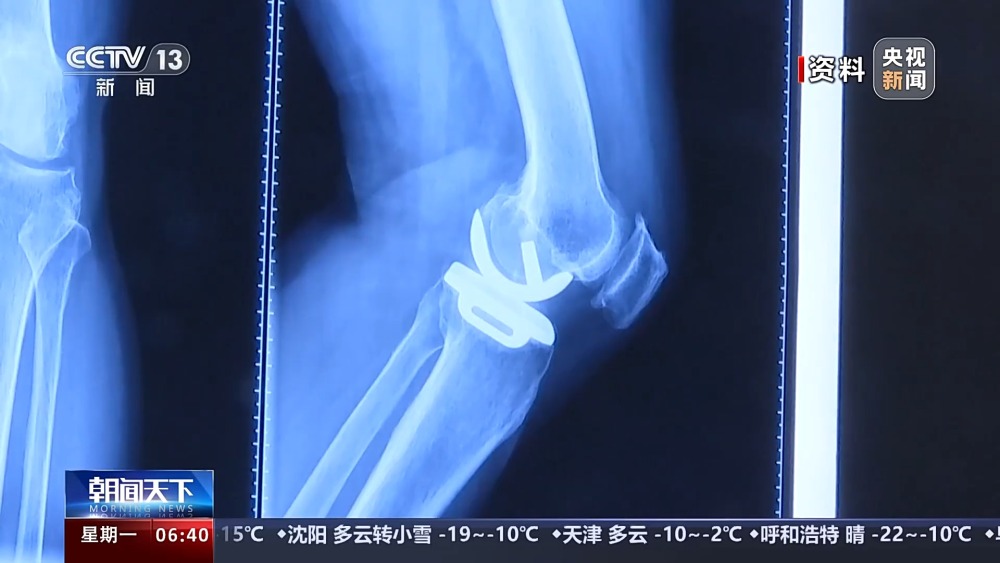

目前,我國有超過1億人患有骨關節(jié)炎,65歲以上人群中,骨關節(jié)炎發(fā)病率接近50%。以前,嚴重骨關節(jié)炎患者主要通過膝關節(jié)置換手術來維持行走等基本功能。膝關節(jié)置換手術存在術后關節(jié)僵硬、長期疼痛等問題。保膝治療包括藥物、理療等保守治療,以及手術治療。

保膝手術主要包括截骨術和單髁置換術,其中截骨術在解決患者疼痛癥狀的同時,阻止下肢異常應力對膝關節(jié)的進一步損傷,膝關節(jié)內所有軟骨韌帶、半月板都得到了保留。內側單髁置換術,使膝關節(jié)外側健康的軟骨和半月板得到了保留,膝關節(jié)內外側的韌帶維持原有狀態(tài),患者康復后,擁有正常的膝關節(jié)功能。